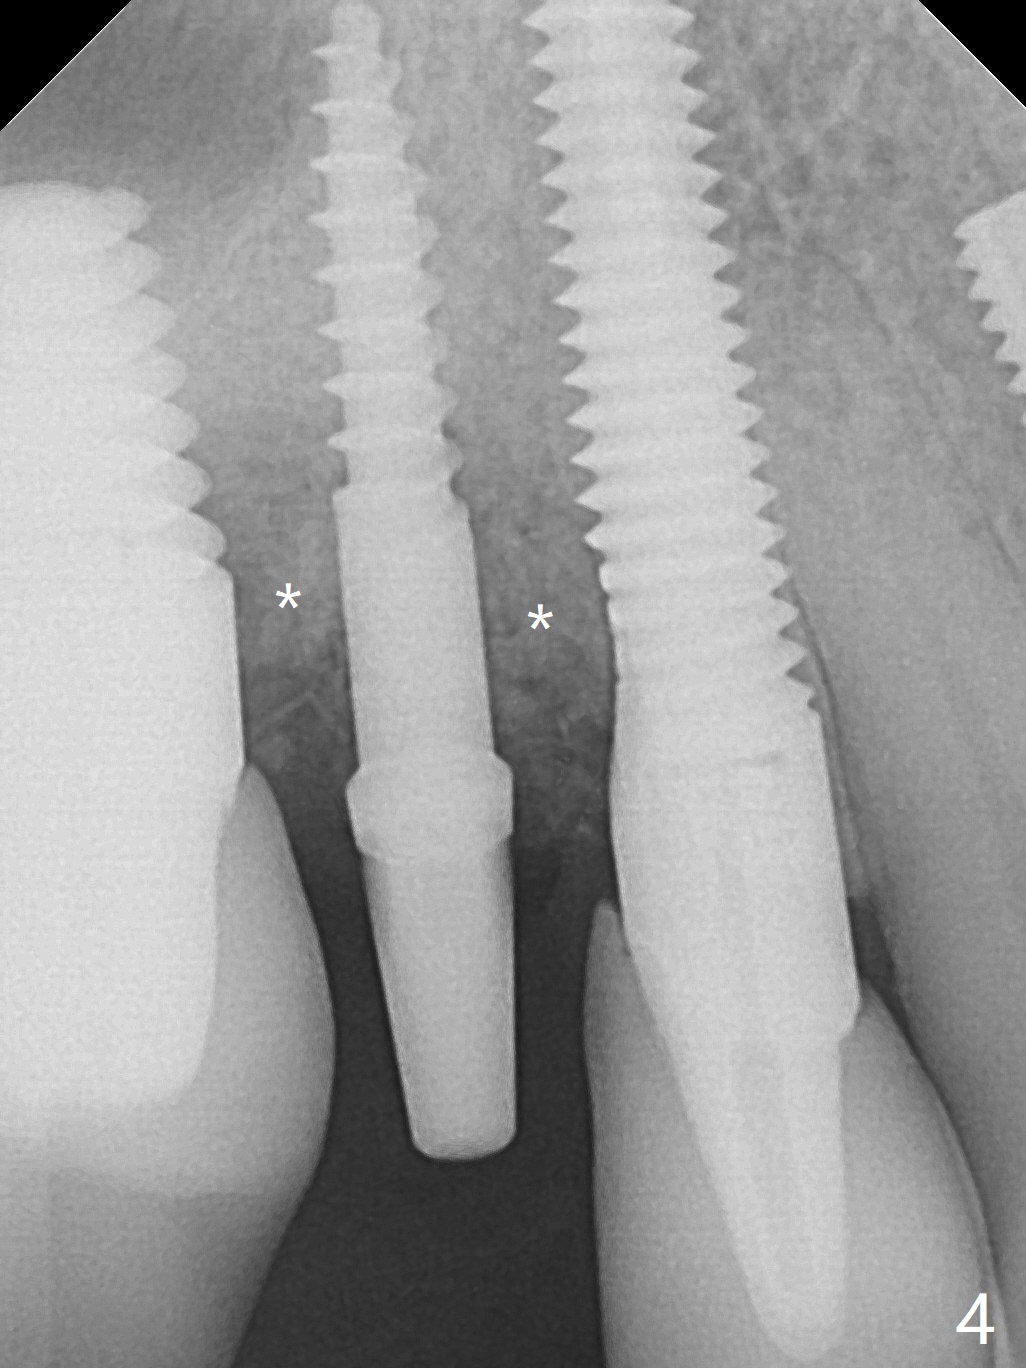

The osteotomy gap at #4 disappears 3.5 months post implant removal with bone graft; the mesiodistal space is 6.6 mm (Fig.1). Incision confirms disappearance of the osteotomy gap. A new osteotomy is established for 10 mm (Fig.2). A 2.5x10(4) mm 1-piece implant is placed with <50 Ncm; since the trimmed implant threads at #5 are exposed (Fig.3), Vanilla graft with Osteogen is placed mesial and distal to the new small implant (Fig.4 *). There is no bone loss 3.5 months postop (Fig.5,6). After cementation of the crown (Fig.7 C) with the thin abutment (*), the patient feels that the crown has mobility. The crown in fact has no clinical mobility; it cannot be removed. After occlusal equilibrium, the patient does not feel the same. The thin 1-piece implant must flex under heavy occlusion. The patient is a bruxer. There is no crestal bone resorption 4 months post cementation (8 months post cementation, Fig.8,9). There is no sign of periimplantitis anymore. The implant remains mobile and symptomatic (chewing pain) 14 months post cementation (Fig.10). There is no bone loss 2 years 4 months post cementation (Fig.11).